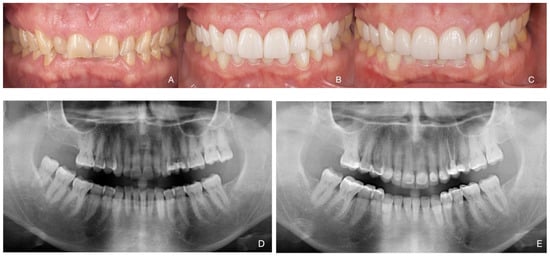

Total Rehabilitation Using Adhesive Dental Restorations in Patients with Severe Tooth Wear: A 5-Year Retrospective Case Series Study

3. Results